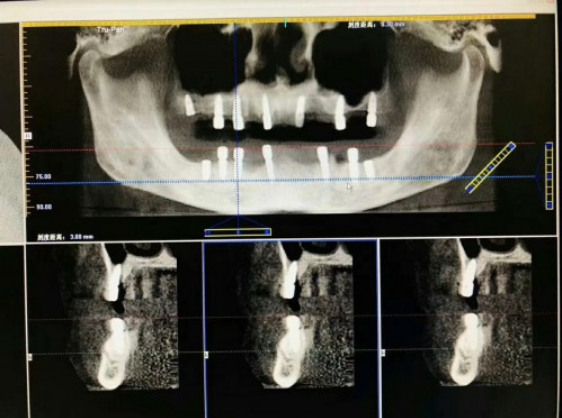

种植牙其实并不能所有人都能种的,为了能让爷爷拥有一口好牙,我还特意在杭牙帮爷爷预定了一次术前检查,看看爷爷的条件是否可以做种植牙手术。杭州牙科医院的医生先给爷爷做了CT,查看了一下口腔的具体情况。好在爷爷一直生活都挺健康的,除了牙齿之外其他的都没有什么问题。在满足一切条件后,定下种牙需要用的部件材料后,就开始安心准备手术了。

杭州牙科医院的种植牙手术采用的是“即刻种植”种植牙体系,俗称微创种植牙技术,这种技术能避免手术过程中产生的不必要伤口,降低感染风险。只是这种微创手术对医生的专业技术和设备都有着严格的要求。给爷爷主刀的医生我们请的是杭牙的刘颖刘主任。整个种植过程仅需大约只花了一个多小时,还是非常快的,爷爷当天就用到了新的牙齿。